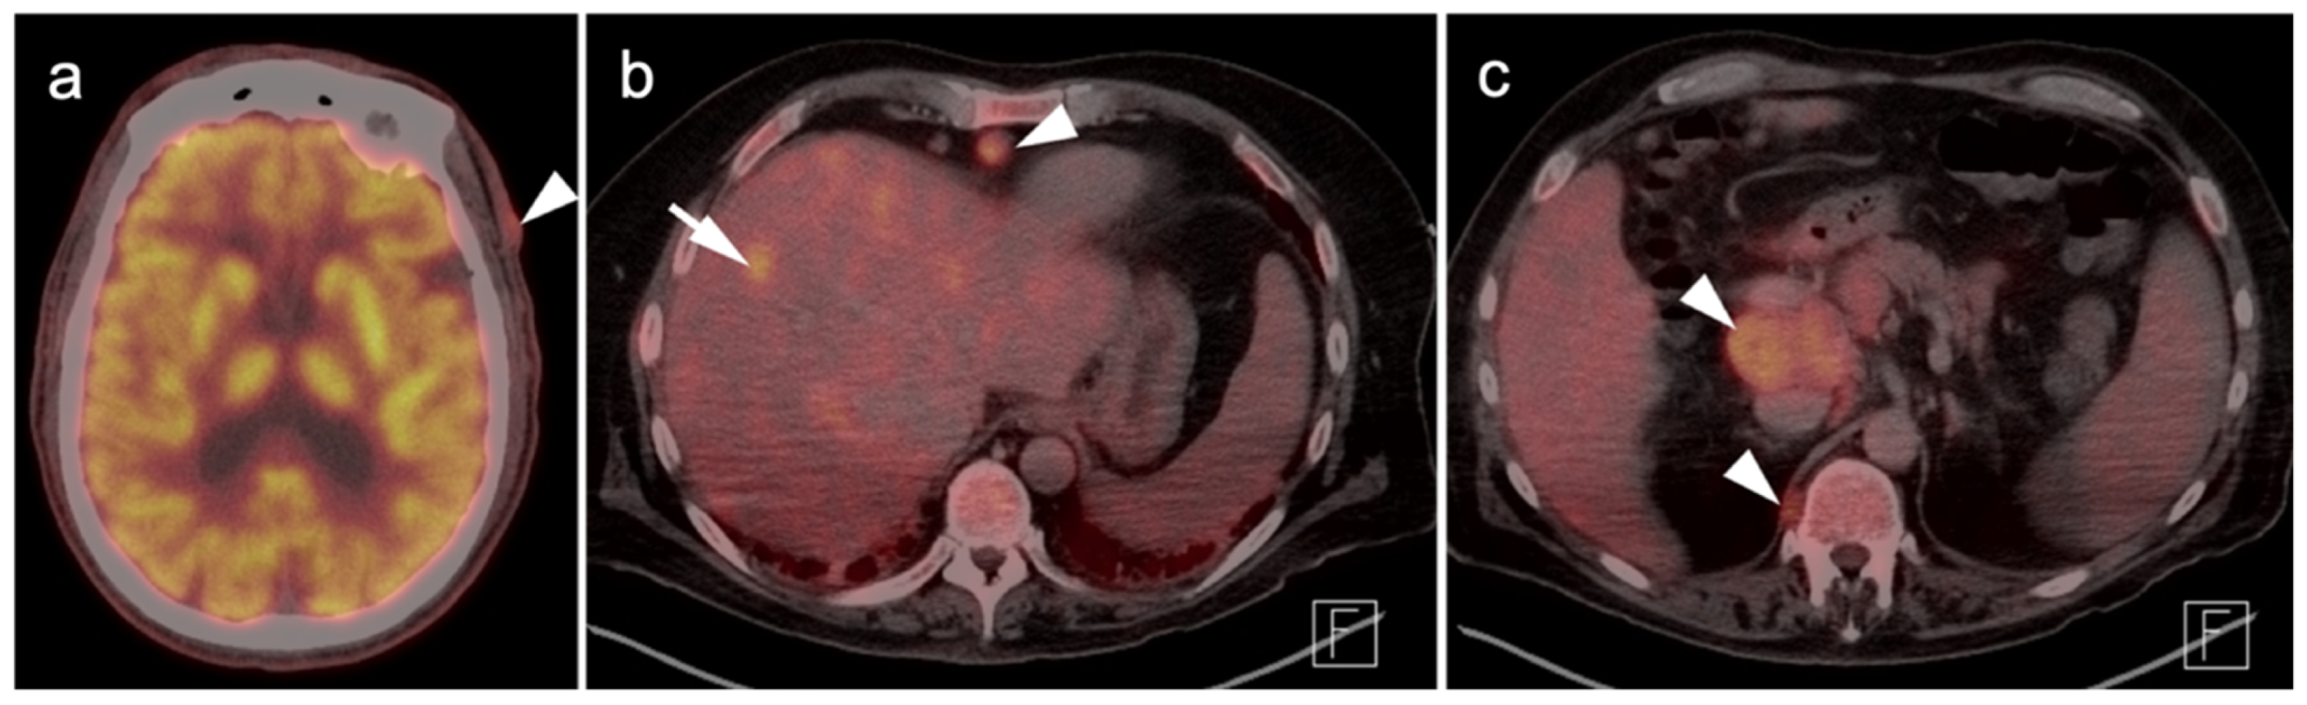

3. Sarcomas

3.1. Soft Tissue Sarcomas

- Roberge, D.; Vakilian, S.; Alabed, Y.Z.; Turcotte, R.E.; Freeman, C.R.; Hickeson, M. FDG PET/CT in Initial Staging of Adult Soft-Tissue Sarcoma. Sarcoma 2012, 2012, 960194. [Google Scholar] [CrossRef] [Green Version]

- Punt, S.E.; Eary, J.F.; O’Sullivan, J.; Conrad, E.U. Fluorodeoxyglucose positron emission tomography in leiomyosarcoma: Imaging characteristics. Nucl. Med. Commun. 2009, 30, 546–549. [Google Scholar] [CrossRef] [Green Version]

- Gao, Y.-J.; Yang, Z.; Yu, J.-Y.; Li, N.; Wang, X.-J.; Zhou, N.-N. Potential application value of PET/computed tomography in retroperitoneal leiomyosarcoma and a literature review. Nucl. Med. Commun. 2021, 42, 800–810. [Google Scholar] [CrossRef]

- Subramaniam, S.; Callahan, J.; Bressel, M.; Hofman, M.S.; Mitchell, C.; Hendry, S.; Vissers, F.L.; Van der Hiel, B.; Patel, D.; Van Houdt, W.J.; et al. The role of 18 F-FDG PET/CT in retroperitoneal sarcomas—A multicenter retrospective study. J. Surg. Oncol. 2021, 123, 1081–1087. [Google Scholar] [CrossRef]